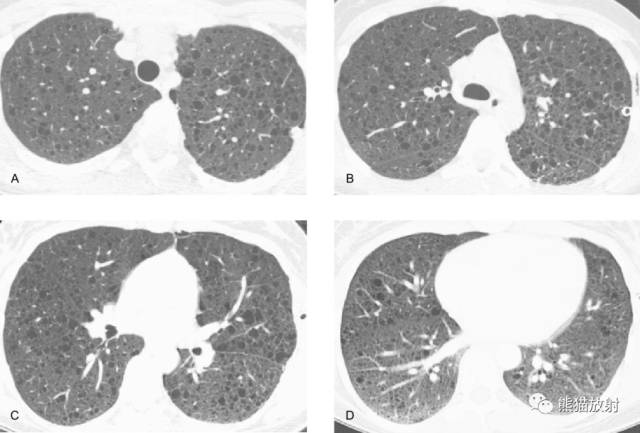

在HRCT上,LAM病例的特征性表现为无数薄壁肺囊肿,周围绕以较正常的肺实质。这些囊肿的直径范围常为2mm~5cm,也可以更大。囊肿的大小倾向于随病变进展而增大。发生在TSC中的LAM与单发LAM表现相同。

在大多数病例中,囊肿弥漫性分布于肺内,无肺区可避免。

在大多数病例中,HRCT上囊肿之间的肺实质正常。

在确定本病中含气囊肿的范围和分布上HRCT优于胸片,在一些胸片正常病例中,HRCT能显示有广泛的异常。